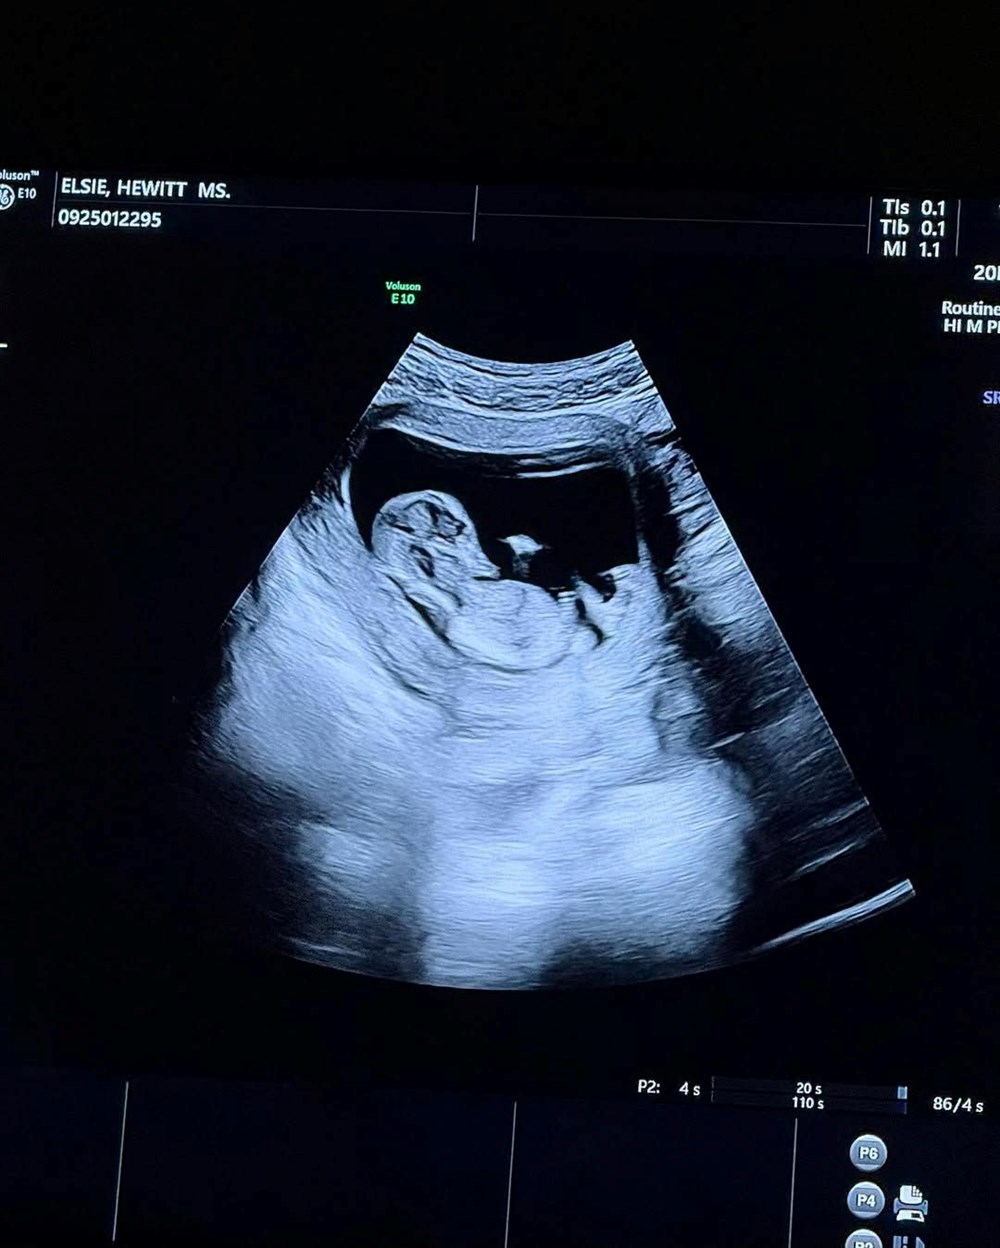

BEBEK GELİYOR

Hewitt, sosyal medya hesabından bir dizi fotoğraf paylaştı ve hamile olduğunu açıkladı.

29 yaşındaki model, paylaştığı karelere "Artık herkes seninle neler yaptığımızı biliyor” notunu düştü.